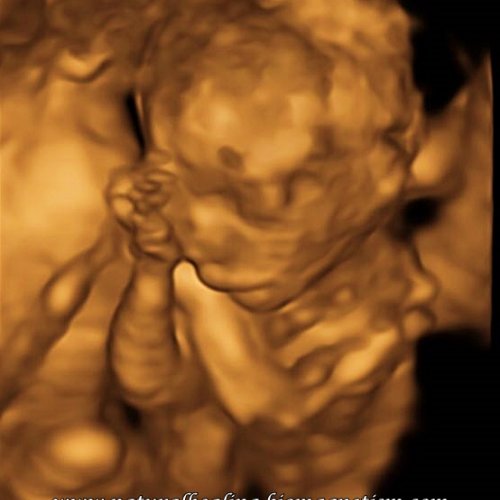

Many were jumping for joy in Ireland recently as abortion will soon become legal there. I had no words really. According to UK's Office of National Statistics, 190,406 babies were aborted in England & Wales alone in 2016. This little boy is my grandson at 15 weeks gestation but current law does not recognise babies as viable beings before 24 weeks - which is also the legal limit for abortion.